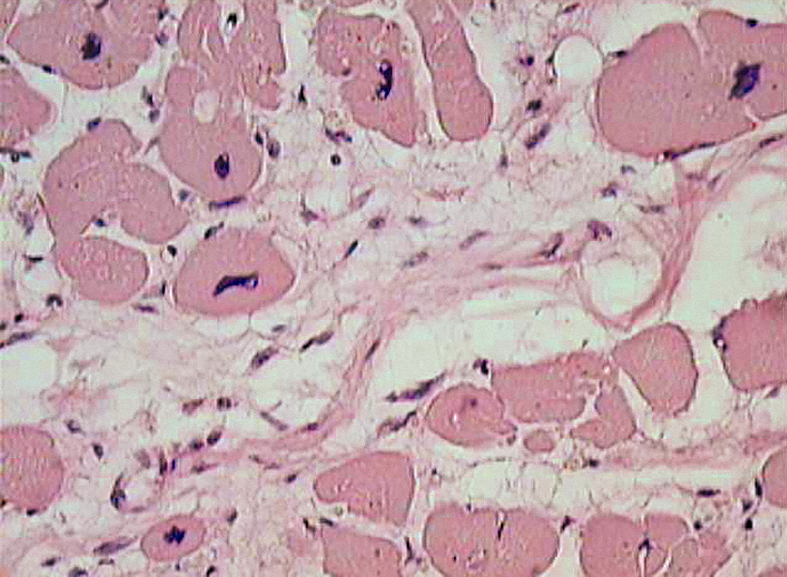

Микропрепараты: Лимфогранулематоз и Нодулярный Склероз

Раздел: Секреты мастерства